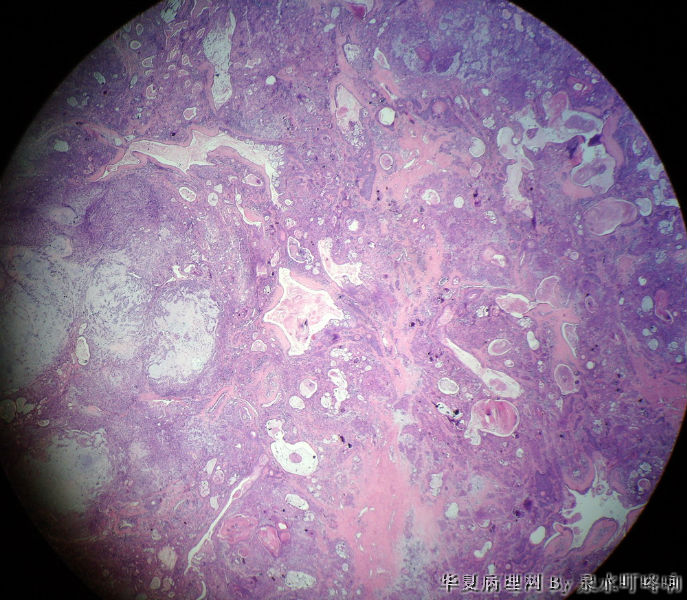

左腮腺肿物

女,38岁,左耳下方肿物,临床诊断:左腮腺肿物。

大体:灰白肿物一个,大小约4×3.5×3厘米,切面灰白,质略软,可见多发囊腔。

(左腮腺)多形性腺瘤

多形性腺瘤(粘液软骨样区域+上皮成分)

瘤组织由多种上皮成分(腺上皮+肌上皮+鳞化上皮)及黏液软骨样基质构成,多形性腺瘤可以囊性变,多结节状分布。

多形性腺瘤,肌上皮、腺上皮增生,鳞化、粘液背景

1、境界清楚

2、两种类型细胞:导管上皮+肌上皮,肌上皮与周围间质有融合现象。

3、伴有角化的鳞状分化。

4、间质:软骨粘液样间质+弹力纤维。

综上:多形性腺瘤。